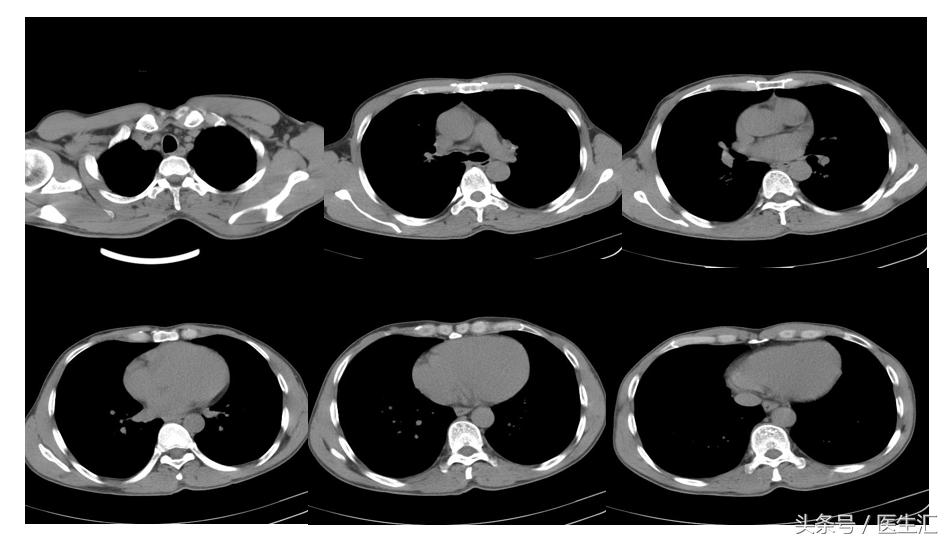

胸部CT

初步诊断:吸入性损伤